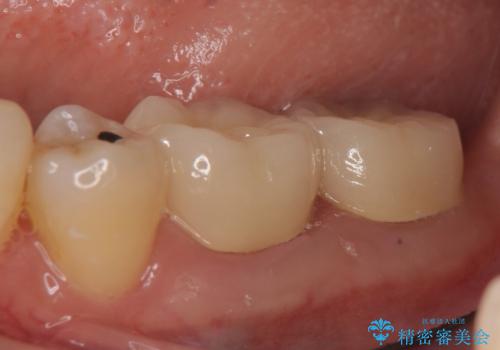

症状の消失を確認後、オールセラミッククラウンによる補綴を行いました。

今回用いたオールセラミッククラウンは、ジルコニアフレームという白い素材の上にセラミックを盛っているため審美性が非常に高いのが特徴です。

またジルコニアは人工ダイヤモンドの材料にも使われているほど高い強度を持っており、そのためオールセラミッククラウンは審美性だけでなく、奥歯やブリッジの補綴も可能とするクラウンです。